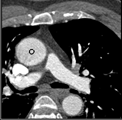

Samples for ascending aorta detection (black circle):

Cluster of candidate points in the ascending aorta.